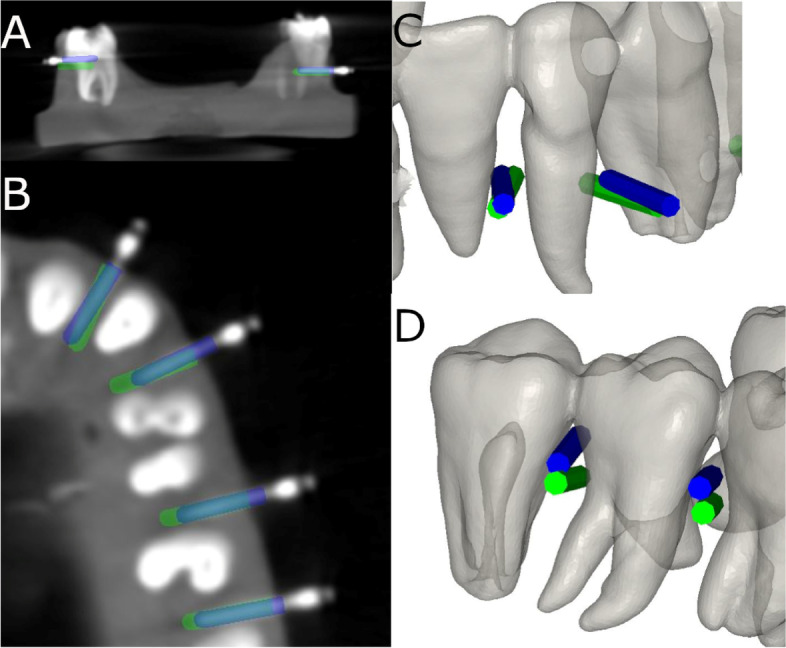

Afterwards, the datasets from the postoperative CBCT scan and the STL digital file were then aligned to assess the deviation angle (as measured in the middle of the cylinder) and horizontal deviation (taken at the coronal entry-point and apical end-point of each orthodontic self-drilling mini-implant) between the planning and the postoperative position (Fig. 5A–D) by an independent observer, using a measure tool of the 3D implant planning software (NemoScan®, Nemotec, Madrid, Spain) (Video illustration: https://youtu.be/9ef06jAuDKU). All these experimental procedures were performed according to the methods conducted in a previous study [23].

Fig. 5.

A–D Deviations measurement procedure between planned (green cylinder) and placed (blue cylinder) orthodontic self-drilling mini-implants in all study groups